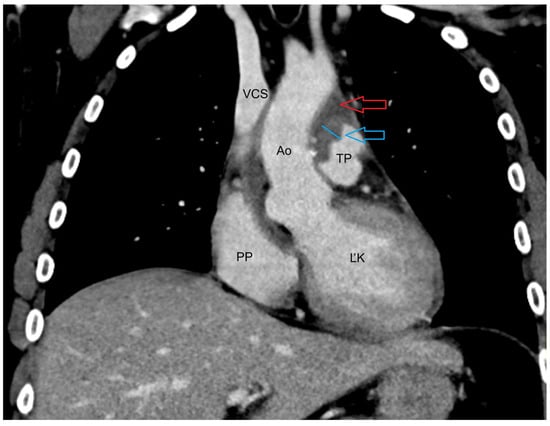

2. Case Presentation